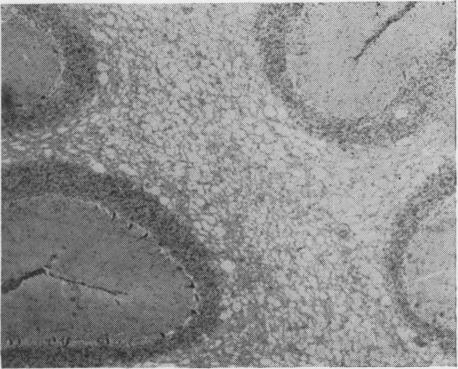

Hulland T J

Can J Comp Med Vet Sci. 1957 Mar;21(3):72-6.